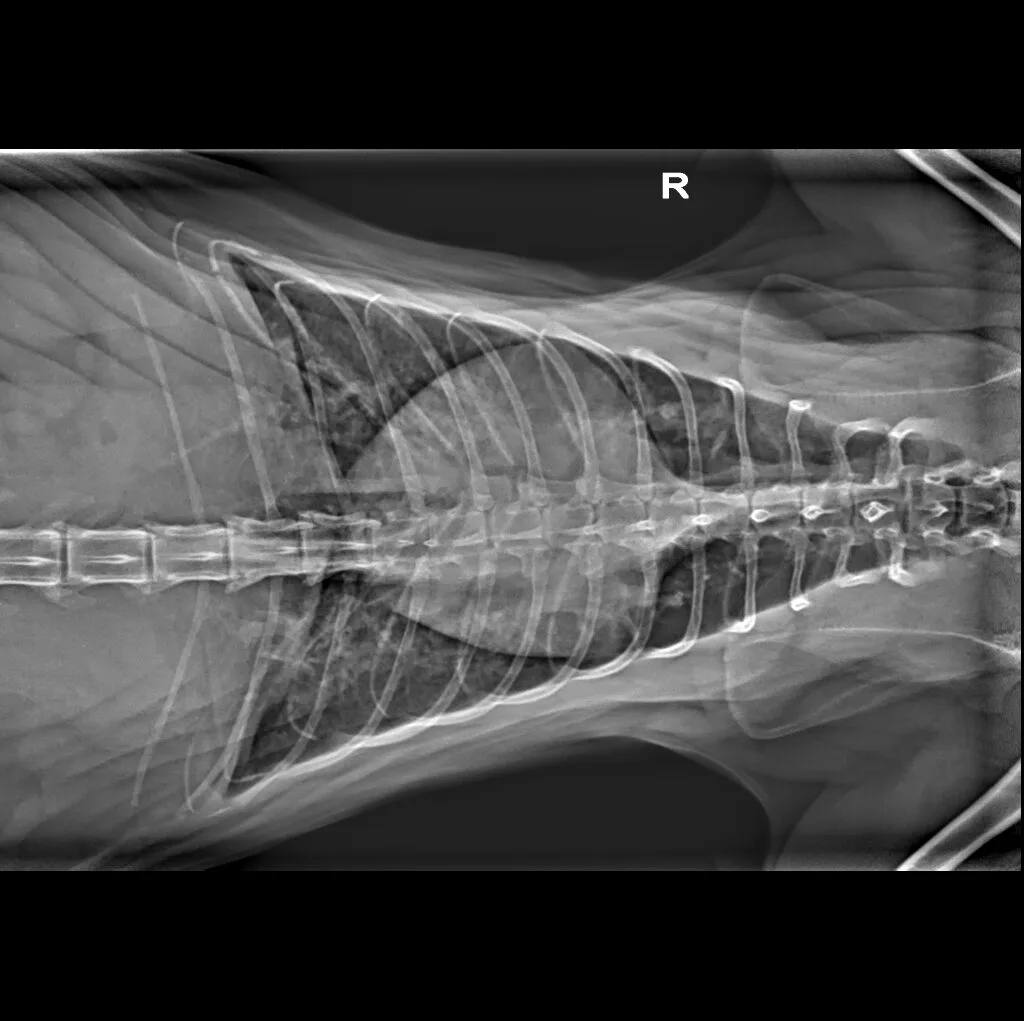

At Grand Ave. Pet Hospital, we utilize digital radiography to diagnose and monitor a wide range of medical conditions in pets. Digital X-rays provide clearer images, faster results, and safer radiation levels, ensuring the best possible care for your furry companion.

Digital radiography offers superior imaging quality and precision compared to traditional X-ray techniques. It allows us to detect hidden health issues early, leading to faster and more effective treatments.

🔹 Lameness & Joint Issues – Identifying fractures, arthritis, and mobility concerns

🔹 Cardiac & Respiratory Conditions – Evaluating heart disease and lung disorders

🔹 Abdominal & Gastrointestinal Issues – Detecting obstructions, tumors, or organ abnormalities